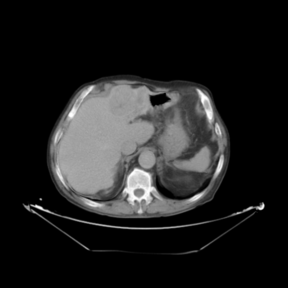

In addition to the previous measurements, the visual outcomes of two of the experiments are shown in [[#img-3|Figures 3]] and [[#img-4|4]], whose purpose is to highlight the most illustrative differences (from a medical point of view) between the results provided by the compared methods. In  [[#img-3|Figure 3]], we observe a normal size of the liver, with discretely irregular contours and homogeneous signal intensity. In hepatic segment II, there is a lesion of 40 mm of maximum axis, encapsulated and with well-defined contours and heterogeneous enhancement in arterial phase (after administration of intravenous contrast), suggestive of hepatocellular carcinoma (HCC). In this slice of the CT scan, we can also observe the aorta that shines in the arterial phase, the lower area of the stomach and the upper area of the spleen. In  [[#img-4|Figure 4]], the liver has a normal size with discretely irregular contours in relation to changes due to chronic liver disease. In hepatic segment IV, a 36 mm diameter focal lesion is identified, which has arterial phase enhancement with a small area of necrosis of 13 mm; it corresponds to a HCC previously chemoembolized with partial necrosis. In this slice of CT, we can also observe the aorta, the gastric chamber and the spleen. When comparing the two methods under study, it can be seen how in  [[#img-3|Figure 3]] the resulting registered datasets are very similar. However, looking closely, it can be noticed that in the right part of the image (left side of the patient) the shape and width of the structures corresponding to the stomach and the spleen in  [[#img-3|Figure 3]](d) match better those in the reference dataset. Likewise, the part of the rib at the upper right of the image is more similar to the same region in the reference dataset by using the proposed method. Regarding the experiment shown in  [[#img-4|Figure 4]], it can be easily appreciated how the geometrical matching (with respect to the reference dataset,  [[#img-4|Figure 4]](a)) of the structures in the right side of the image (specially the gastric chamber) is visually more satisfactory in  [[#img-4|Figure 4]](d). Moreover, the area of tumor necrosis which results from the proposed method is also slightly better aligned.

In addition to the previous measurements, the visual outcomes of two of the experiments are shown in figures Fig.[[#img-3|3]] and Fig.[[#img-4|4]], whose purpose is to highlight the most illustrative differences (from a medical point of view) between the results provided by the compared methods. In Fig.[[#img-3|3]], we observe a normal size of the liver, with discretely irregular contours and homogeneous signal intensity. In hepatic segment II, there is a lesion of 40 mm of maximum axis, encapsulated and with well-defined contours and heterogeneous enhancement in arterial phase (after administration of intravenous contrast), suggestive of hepatocellular carcinoma (HCC). In this slice of the CT scan, we can also observe the aorta that shines in the arterial phase, the lower area of the stomach and the upper area of the spleen. In Fig.[[#img-4|4]], the liver has a normal size with discretely irregular contours in relation to changes due to chronic liver disease. In hepatic segment IV, a 36 mm diameter focal lesion is identified, which has arterial phase enhancement with a small area of necrosis of 13 mm; it corresponds to a HCC previously chemoembolized with partial necrosis. In this slice of CT, we can also observe the aorta, the gastric chamber and the spleen. When comparing the two methods under study, it can be seen how in Fig.[[#img-3|3]] the resulting registered datasets are very similar. However, looking closely, it can be noticed that in the right part of the image (left side of the patient) the shape and width of the structures corresponding to the stomach and the spleen in Fig.[[#img-3|3]](d) match better those in the reference dataset. Likewise, the part of the rib at the upper right of the image is more similar to the same region in the reference dataset by using the proposed method. Regarding the experiment shown in Fig.[[#img-4|4]], it can be easily appreciated how the geometrical matching (with respect to the reference dataset, Fig.[[#img-4|4]](a)) of the structures in the right side of the image (specially the gastric chamber) is visually more satisfactory in Fig.[[#img-4|4]](d). Moreover, the area of tumor necrosis which results from the proposed method is also slightly better aligned.